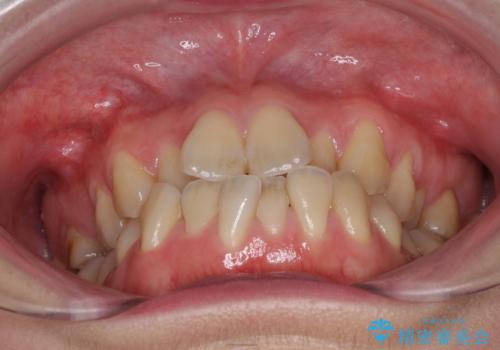

ハーフリンガル 反対咬合の改善

- 前歯の反対咬合を気にして来院された患者様です。

目立ちにくい装置での治療をご希望とのことで、上顎が裏側装置、下顎が表側装置のハーフリンガルにより矯正治療を行うこととしました。

下顎の歯列全体を後方に動かす場合、さまざまリスクを伴うため慎重に行う必要があり、さらには移動量に限界があるため、治療計画は無理のないものとしなければなりません。